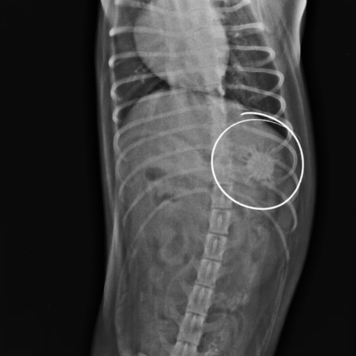

На RG в желудке собаки был обнаружен круглый предмет. Ветеринарный врач Клиники БАРС Анна Сергеевна Кашина приняла решение о немедленном проведении гастроскопии, т.к. инородное тело еще можно было извлечь при помощи эндоскопа. Находкой оказался мягкий резиновый мячик.